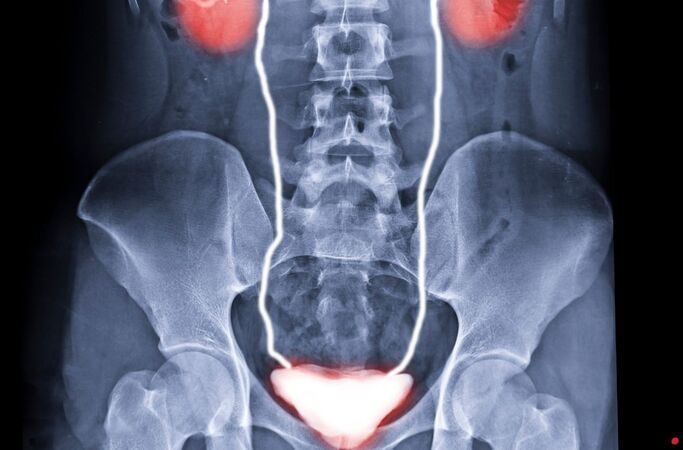

İdrar Yolu Enfeksiyonu Nedir?

İdrar yolu enfeksiyonu (İYE), idrar yollarında bakterilerin çoğalması sonucu ortaya çıkar. Çoğunlukla bağırsak kökenli E. coli bakterisi bu enfeksiyonlara neden olur.

Sistit: Mesanenin iltihaplanmasıdır. Kadınlarda en sık görülen enfeksiyon tipidir.

Üretrit: İdrar yolunun (üretra) iltihaplanmasıdır. Cinsel yolla bulaşan hastalıklarla da ilişkili olabilir.

Piyelonefrit: Böbreklere kadar ilerleyen enfeksiyondur. Yüksek ateş ve bel ağrısıyla seyreder, acil tedavi gerektirir.